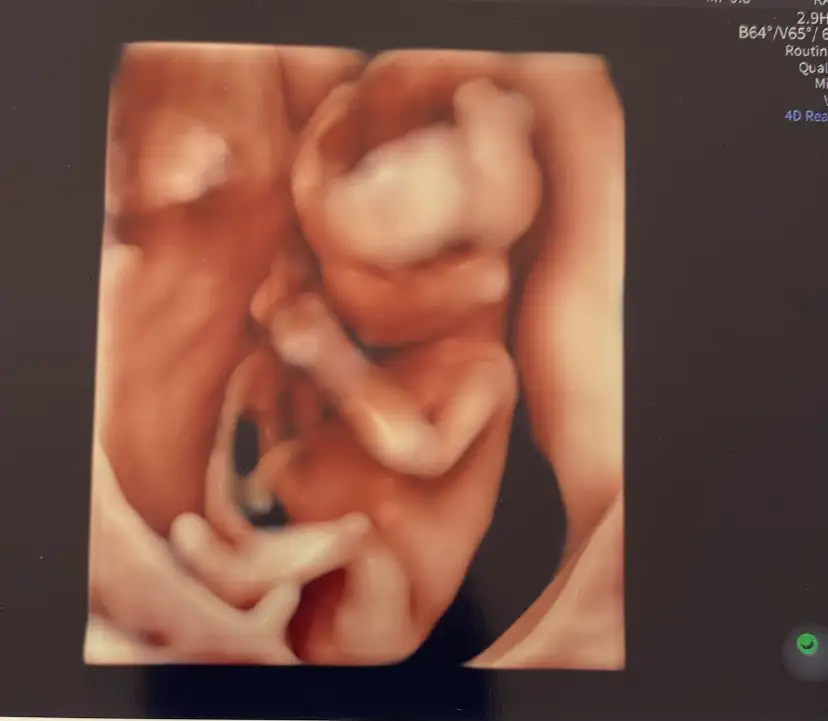

Selammm teyzelerim ben büyüyorummm:) 13+4 olmuşum. Sizde durumlar nasıl 🎀🧿🙏🏻

Eklentiler

• IMG_5690.webp

IMG_5690.webp

11,8 KB · Görüntüleme: 73